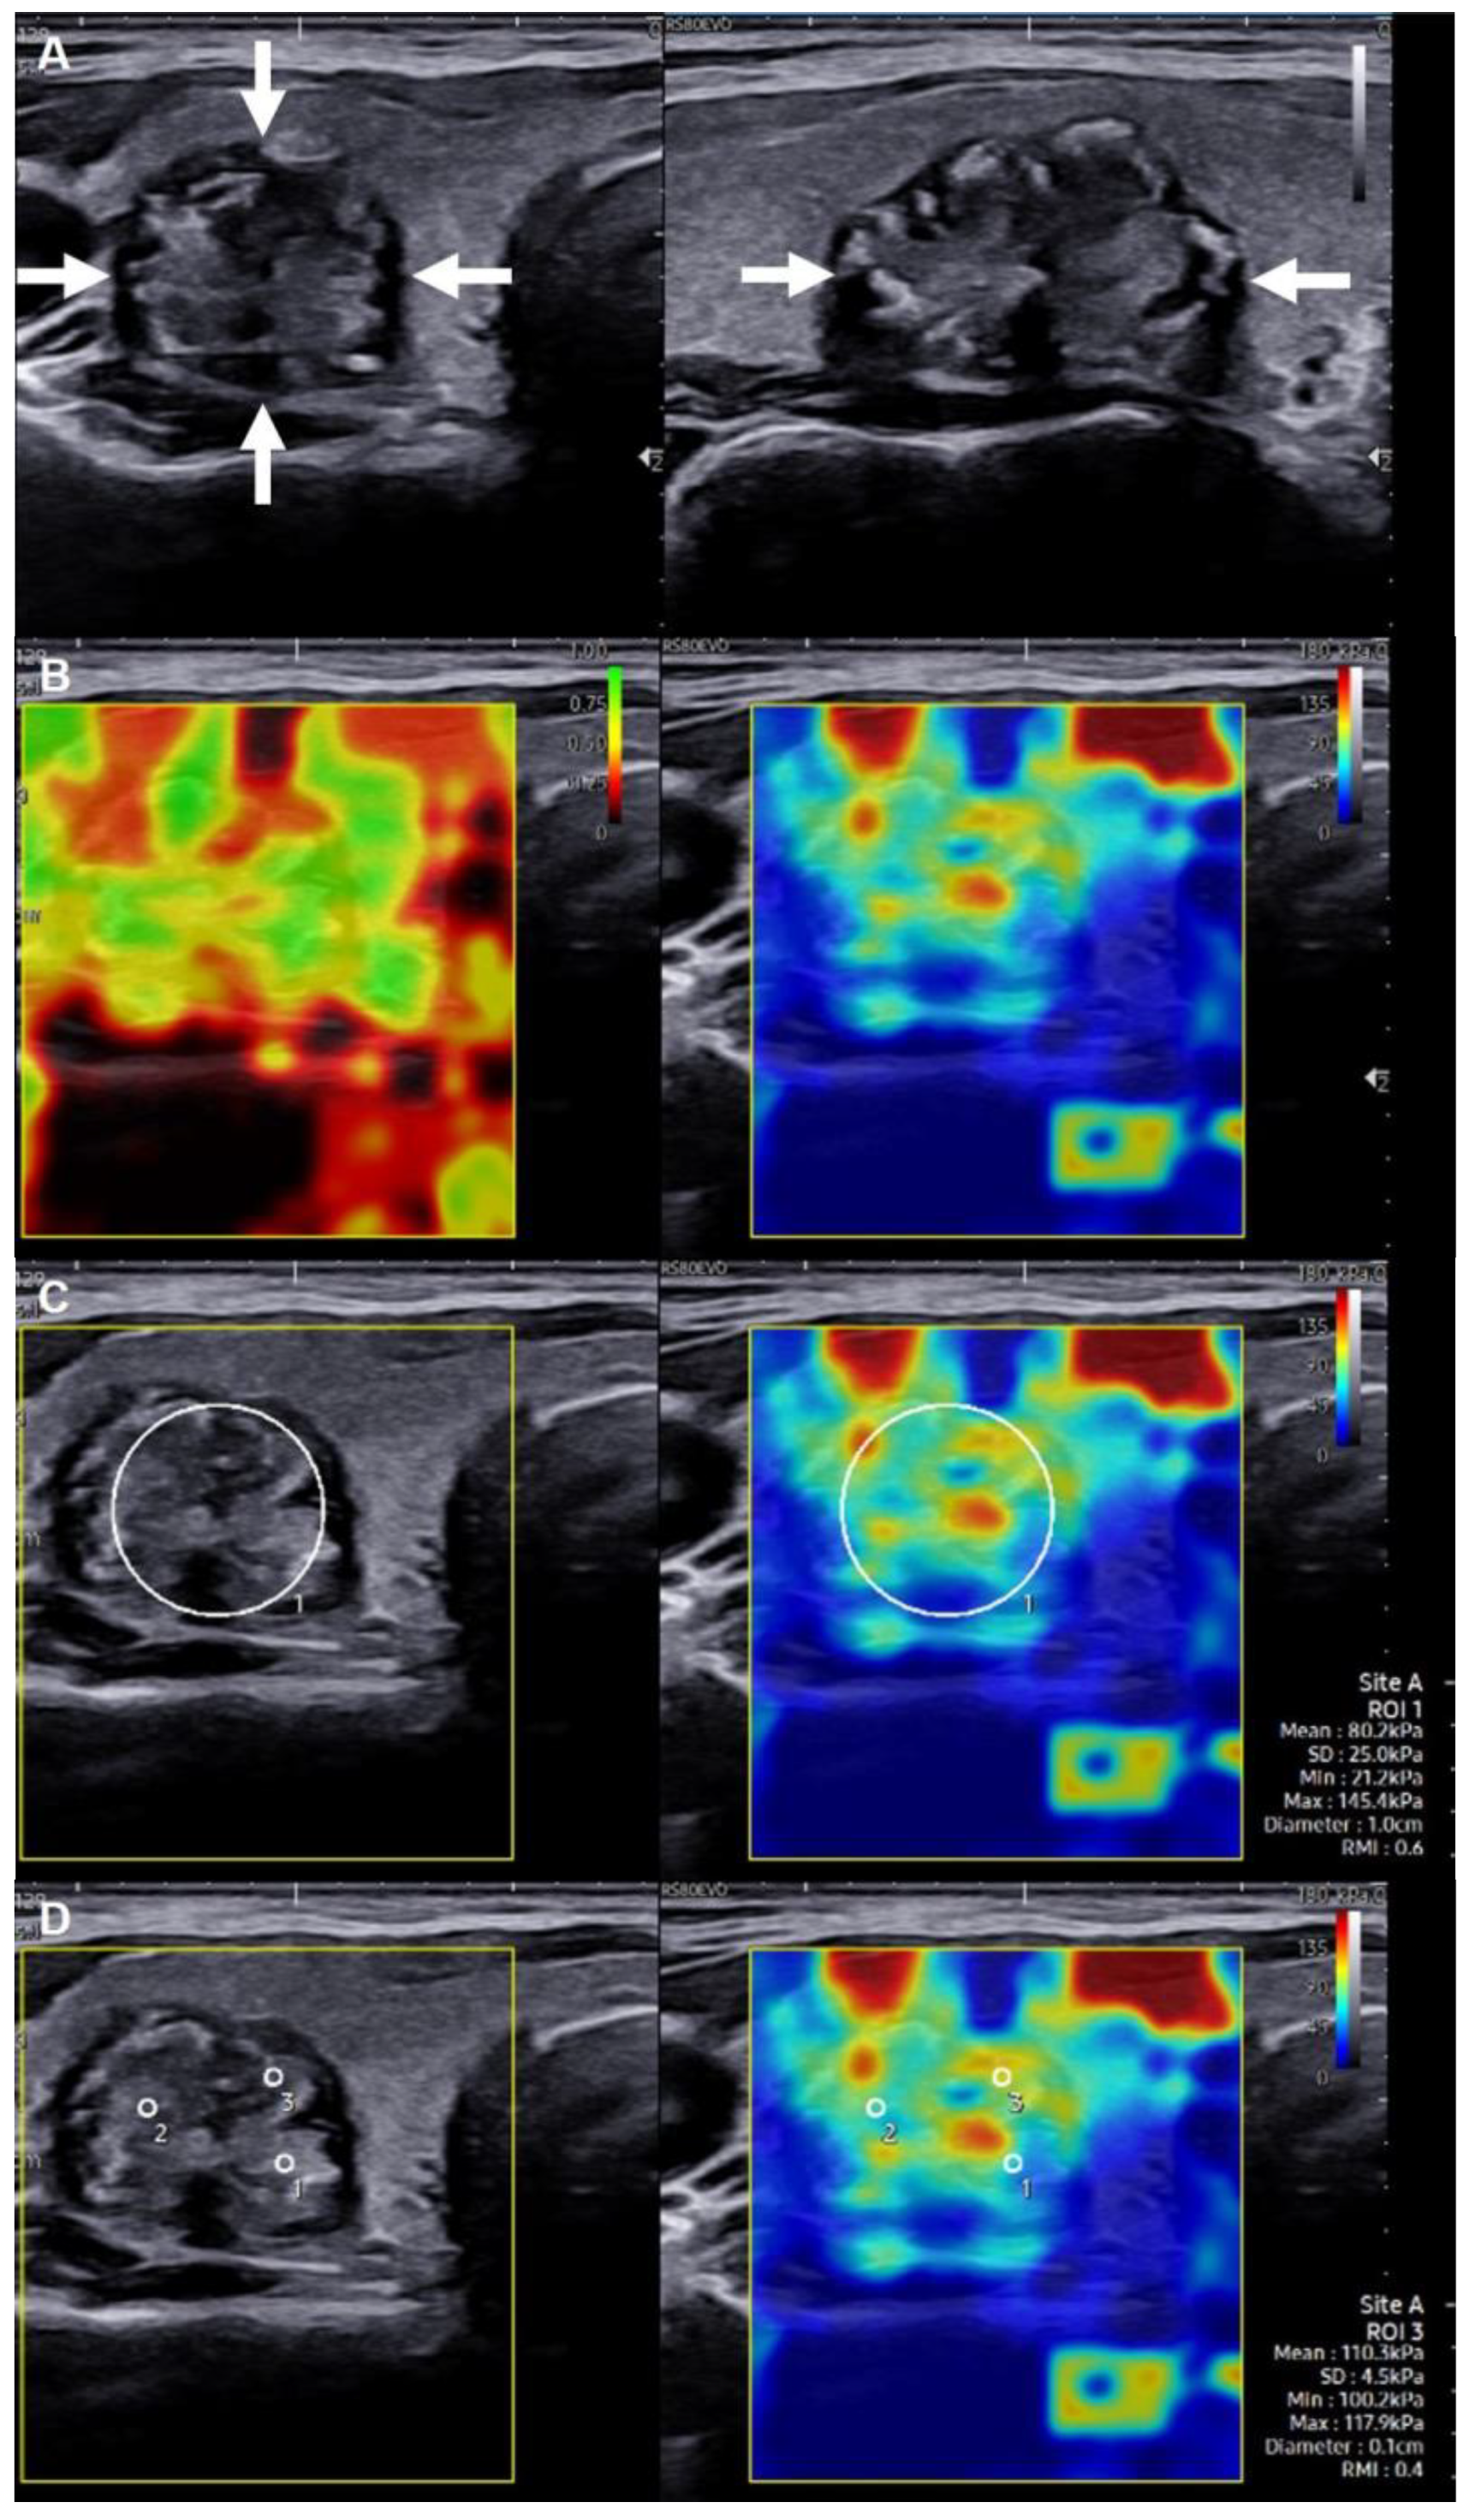

2.2. SWE Evaluation and Measurement